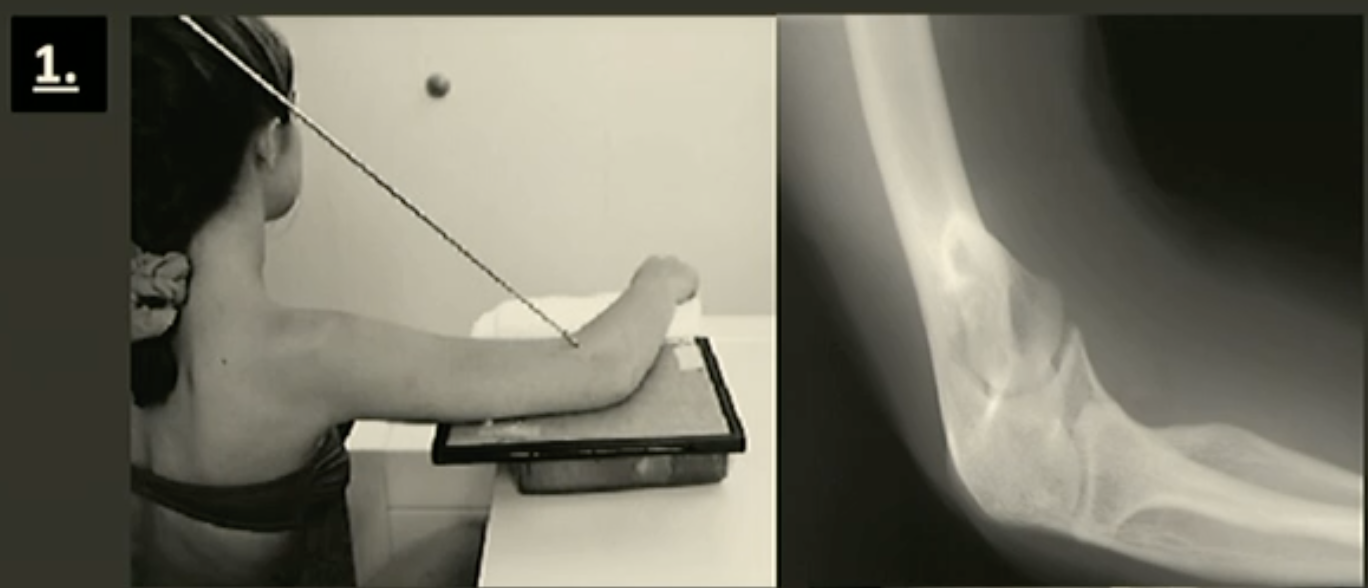

Lateral Elbow

Fine FS, 100cm

60kVp/3mAs

Straight tube

CR: Elbow joint